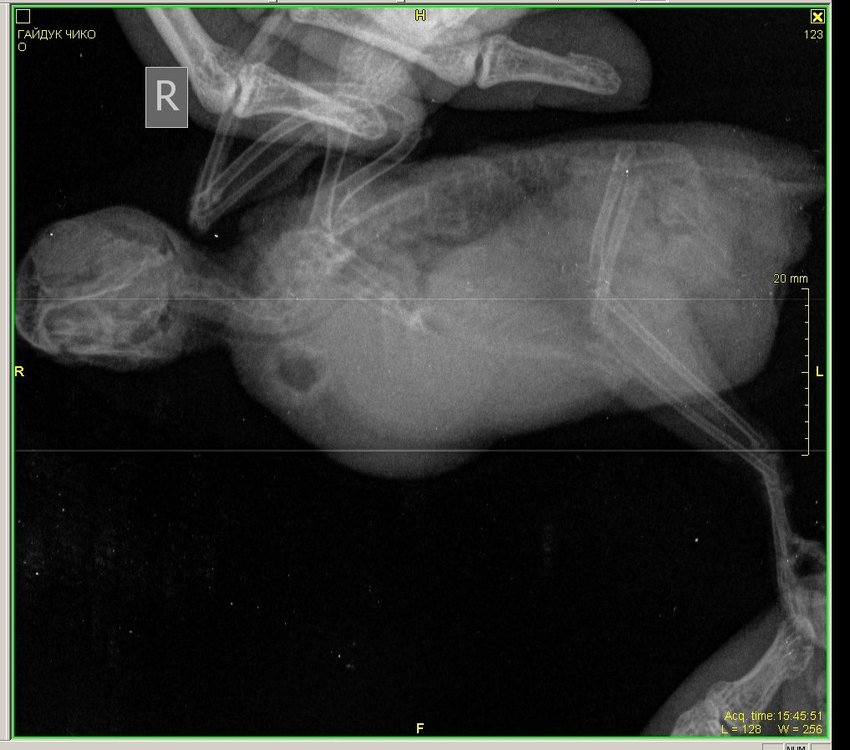

Здравствуйте, корелла самка , возраст 1 год 1 месяц. Вес 100 гр. Поведение - активная , ест, пьет. Оперение нормальное. Питание - овощи, фрукты даю, но практически не ест, каша без молочная детская, чумиза, есть копошилка, сепия, минеральный камень, скелетин с серой, бентонит кормовой, Рио для средних попугаев. Уф лампа есть , световой день 12-13 часов. Весь день летает. Взята была девочка у заводчика в возрасте 3 месяцев, заводчик настойчиво рекомендовала давать песок Рио и рисовую кашу и гречку с желтком яйца, что я и делала 4 раза в неделю, потом я выяснила, что это давать нельзя, и сразу же все убрала и не даю уже около месяца. Первые подозрения на плохое самочувствие были на постоянные вытягивания шеи, иногда трясет головой, умывается очень часто, делая при этом нервные движения при очистке Перьев. Самый основной симптом жидкий помет практически всегда. 12 августа она снесла яйцо ночью, утром я сразу же его выкинула и отвезла к орнитологу. При осмотре орнитологом она сказала , что деформированы носовые ходы , ожирение. Рекомендован был рентген, по рентгену орнитолог сказала , что к попугая : Аэросаккулит(воспаление воздушных мешков), пневмония, нефрит, гепатомегалия, повышенная плотность костей связана с гиперестрогенизмом Были сданы анализы , пока еще не готовы , один готов , вот результат: Цвет: светло-зеленый Консистенция: жидкий Соотношение микроорганизмов: подвижные кокки 50%, палочки 50%, стрептококки Кристаллы мочевой кислоты в большом количестве Нейтральный жир умеренно Билирубин отсутствует Жирные кислоты отсутствуют Соли жирных кислот отсутствуют Крахмал внеклеточный в большом количестве Крахмал внутриклеточный отсутствует Лейкоциты более 10 в поле зрения Эритроциты более 20 в поле зрения Эпителий клоаки в большом количестве Эпителий кишечный в большом количестве Слизь присутствует Дрожжи в большом количестве Простейшие не обнаружено было назначено лечение: Амоксиклав/ Флемоклав/ Экоклав (250 мг) - 1 таблетку растворить в 3 мл воды, давать / 0.2 мл, каждые 12 часов в течение месяца. Целекоксиб (200 мг) 1 капсулу растворить в 10 мл воды, давать по 0.05 мл в клюв 1 раз сутки в течение 14 дней Тербинафин таблетки 250 мг - 1 таблетку растворить в 5 мл воды, давать по 0.03 мл 1 ра в 24 часа в течение месяца. Кальций глюконат 100 мг/мл по 2-3 мл в поилку на 50 мл воды 15 дней. Гептрал/Самеликс в обычной аптеке 400 мг/5 мл по 0.1 мл в день месяц Если здесь есть орнитологи, прошу помогите пожалуйста, я была на консультации 3 врачей, я боюсь давать своей птичке Амоксиклав и тербинафин целый месяц. Не много ли это ? Как вы считаете ? И пожалуйста посмотрите рентген умоляю, скажи , что вы видите ? Насколько плохой анализ помета ? И насколько серьезны поставленные диагнозы? И возможно ли это вылечить? Остальные анализы как придут, я приложу фотографии.

Здравствуйте, нужна помощь! Попугай волнистый, Чико. Возраст - 1,9 3 июня начал без остановки чесать попу, выдергивать перья сзади, вести себя беспокойно. 4 июня отвезла к врачу-орнитологу Полозу, взял мазок из зоба и посмотрел кал под микроскопом - определил Гельминтоз, выписал метронидазол 10 дн, решила показать др врачу - Грязнову. 5 июня - отвезла, глянул в микроскоп калл - сказал, что "единичные случаи паразитов", добавил к лечению Нистатин, посоветовал рентген, сделала рентген, но врачам из Минска не показывала , тем,у которых была на приеме, показала знакомому ветеринару -Валерии Сороке, на ее взгляд возможны проблемы с легкими, вчера заметила, что Чико чихнул мокрым! Также сейчас у него зеленый помет, возможно от метронидазола. Совсем я в рестерянности, продолжать лечить глистов? или лечить легкие? Валерия прописала следующие препараты:1. амоксиклав 125 мг 0.2 мл 2 раза в день 14 дней ( 1/2 табл растворить в 2 мл воды) 2. флуканазол 50 мг внутрь 1/10 капс 1 раз в день 14 дней 3. метронидазол 4. иммунофан Помогите поставить точный диагноз по снимку, у нас как таковых орнитологов нет... Сейчас поведение птицы: веселый, активный, кушает хорошо, чешется, чешет попу, чихи мокрые редко.